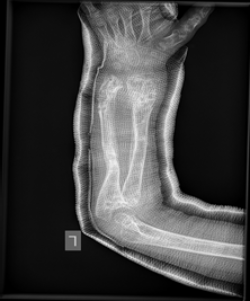

Olier’s disease

The images show a case of Olier’s disease which had a short and deformed forearm. He underwent surgical intervention by Dr. Zenios with the use of external osteosynthesis.

External osteosynthesis